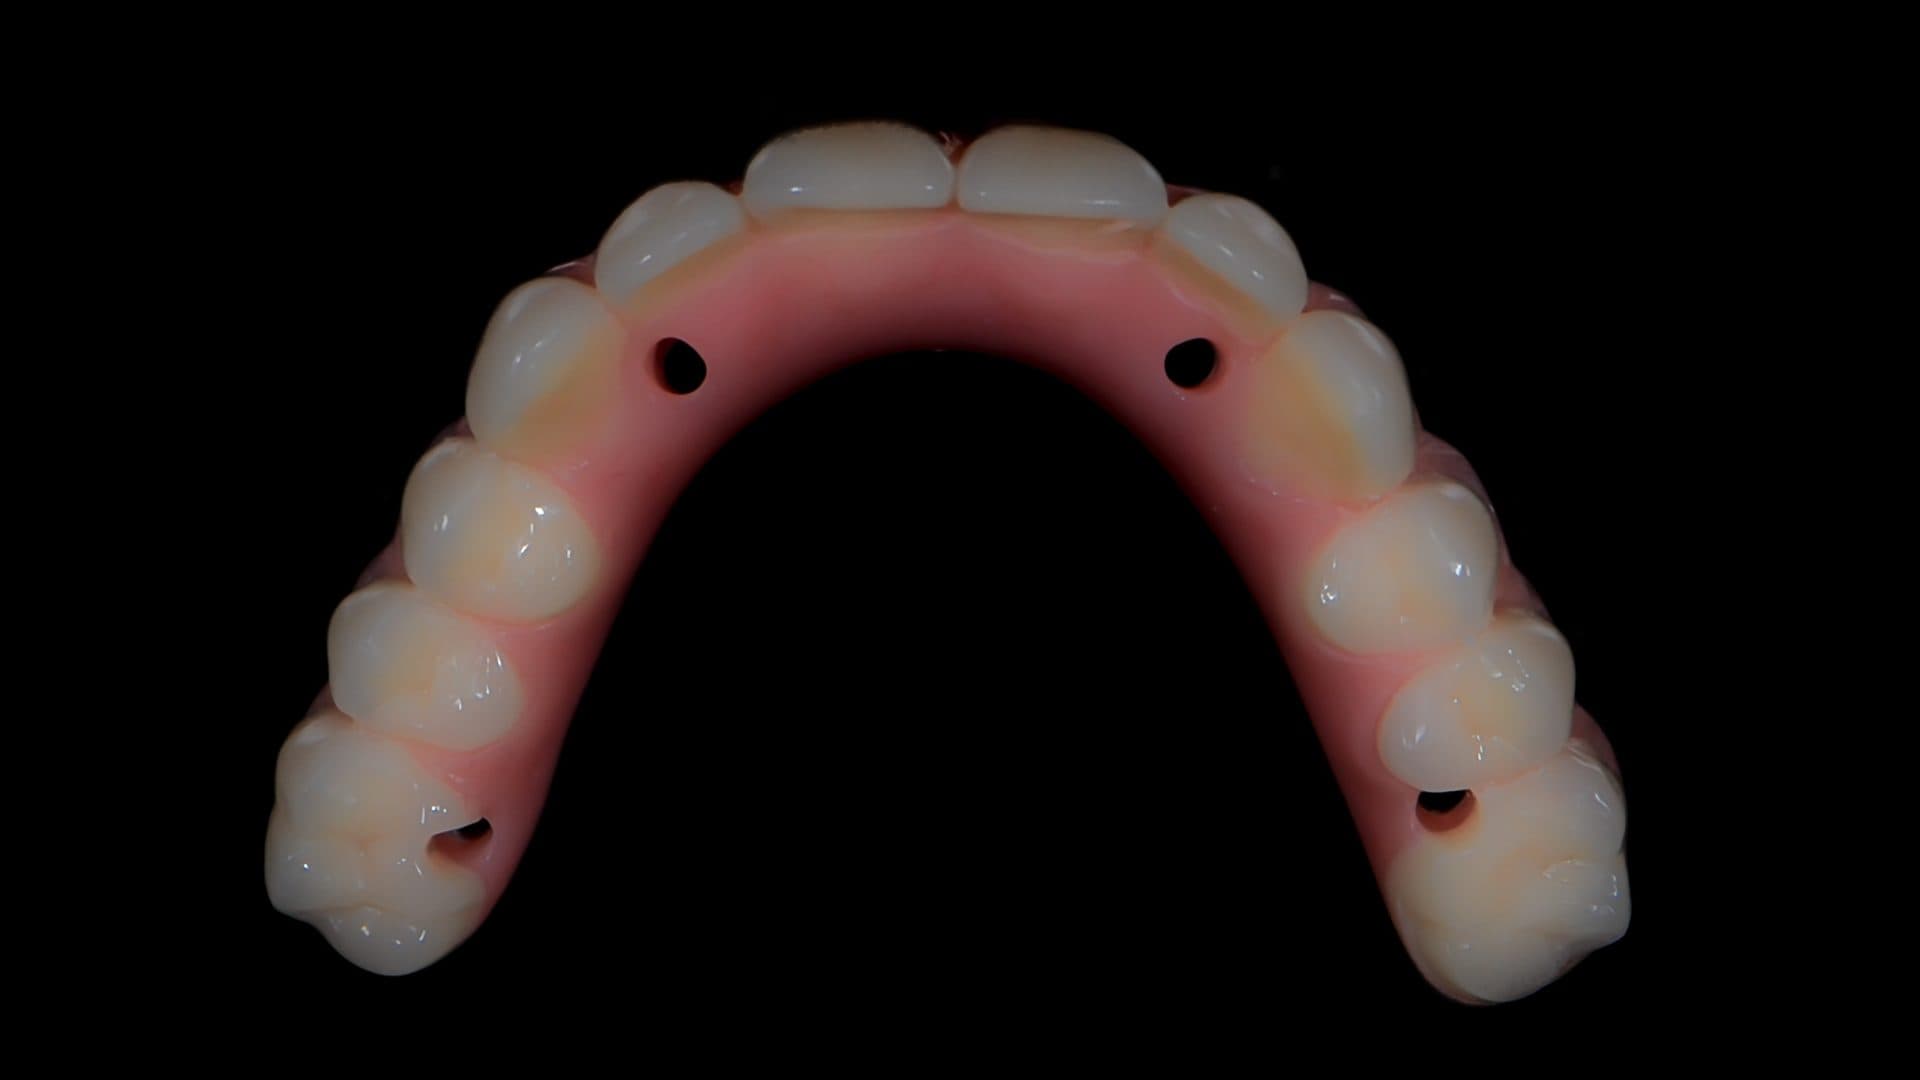

Here is a graphical overview of the ideal situation compared to poor standards with All-on-4 Plus® dental implants.

Ideal Situation

Poor Standards